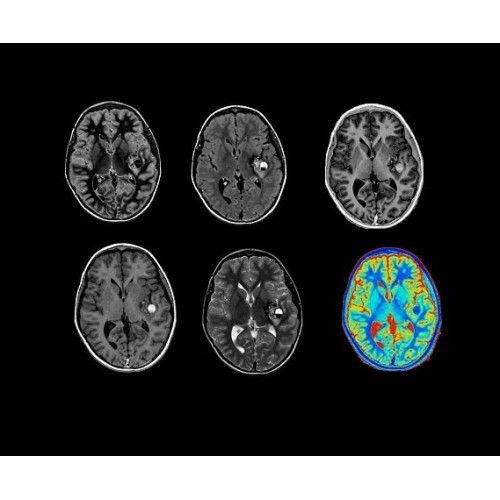

Система SIGNA PET/MR предлагает впечатляющие клинические возможности и открывает доступ к наиболее полным пакетам программных приложений.

Новейшая платформа SIGNA Works4 повышает производительность ключевых технологий визуализации GE Healthcare. SIGNA Architect поставляется с предустановленными стандартными приложениями. Расширенные функции SIGNA Works с возможностью обновления позволят устанавливать новые приложения в соответствии с растущими потребностями вашей клинической практики.

Стандартный пакет приложений SIGNA Works позволит вам достичь желаемых результатов в клинической практике благодаря набору высокоэффективных средств визуализации. Программные приложения, входящие в состав данных клинических пакетов, включают широкий спектр контрастов, функции обработки 2D- и 3D-данных, а также возможность коррекции артефактов движения. SIGNA Works предоставляет набор инструментов, необходимых для проведения эффективного клинического исследования.

• Специальный пакет приложений для измерения и сравнения объемных изображений ЦНС с нормами поможет вам в диагностике нейродегенеративных заболеваний, а дополнительные инструменты визуализации — в постановке точного диагноза с помощью бета-амилоидов и радиоизотопных маркеров ФДГ.